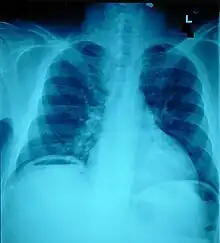

Ten percent of people with polytrauma who had no signs of abdominal injury did have evidence of such injuries using radiological imaging.[1] Diagnostic techniques used include CT scanning, ultrasound,[1] and X-ray.[7] X-ray can help determine the path of a penetrating object and locate any foreign matter left in the wound, but may not be helpful in blunt trauma.[7] Diagnostic laparoscopy or exploratory laparotomy may also be performed if other diagnostic methods do not yield conclusive results.[5]